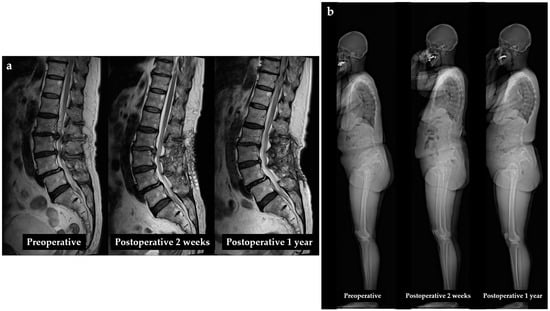

3.6. Representative Case